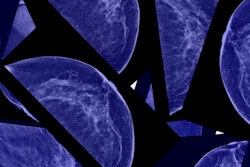

The American College of Physicians (ACP) has shifted its guidance on breast screening to a more conservative approach. The ACP is now recommending that women should start breast cancer screening at the age of 50, not 40, and attend every other year, according to new guidance published April 8 in the Annals of Internal Medicine.

The ACP's position is a change from its 2015 guidance, which advised average-risk women with no symptoms of disease to start biennial screening at age 40, and is in line with the current U.S. Preventive Services Task Force (USPSTF) recommendation. According to the ACP, when compared with annual screening, biennial mammography screening shows no significant difference in breast cancer mortality and reduces screening harms: Women screened yearly receive more abnormal results that are not actually cancer compared with those screened every other year (7% versus 4.8%).

"These false-positive findings result in biopsies and surgeries that would otherwise not have been necessary," the ACP said.

The organization does state that women between the ages of 40 and 49 should be in discussion with their doctors about breast cancer screening, as should those who are at higher risk due to prior abnormal screening results or genetic mutations.

"Beginning at age 40, average-risk women without symptoms should discuss with their physician the benefits, harms, and their personal preferences of breast cancer screening with mammography before the age of 50," ACP President Dr. Ana María López said in a statement.

The ACP also noted that women of average breast cancer risk who are 75 years and older, or those with a life expectancy of 10 years or less, should discontinue breast cancer screening. Finally, it suggested that in average-risk women of all ages, physicians should not use clinical breast exam to screen for cancer.